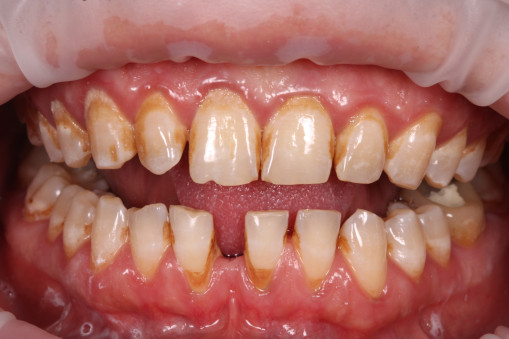

А прежде, чем вы посмотрите фотографии «до» и «после» лечения слизистой оболочки полости рта, проведенных в нашей клинике, хочу поблагодарить большое количество наших пациентов, которые поверили, прониклись нашей концепцией, и мы вместе, именно вместе победили болезни десны, гингивит и пародонтит!

До/после лечения